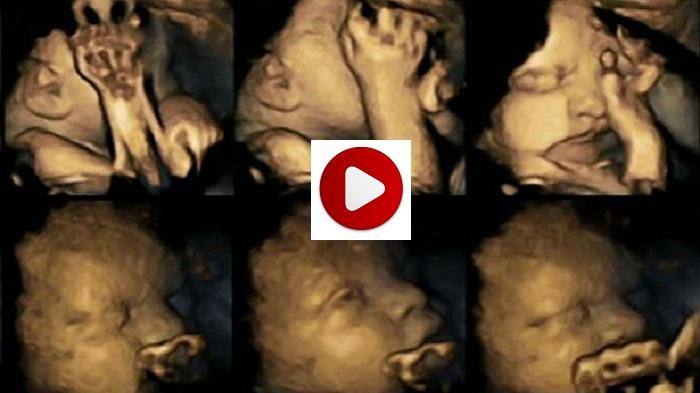

BANJARMASINPOST.CO.ID - Gambar dramatis diperlihatkan mengenai kondisi janin yang berada di dalam rahim ibu yang perokok.

Para ilmuwan percaya, mereka dapat menunjukkan efek dari merokok pada janin di dalam kandungan melalui gerakan kecil di wajah mereka.

Para peneliti telah menggunakan USG empat dimensi (4D) untuk menghasilkan gambar tersebut.

Setelah mempelajari hasil USG mereka pada 24, 28, 32 dan 36 minggu kehamilan, dia mendeteksi bahwa janin yang ibunya merokok terus menunjukkan tingkat signifikan lebih tinggi pada gerakan mulut dan menyentuh daripada yang dilakukan oleh non-perokok.